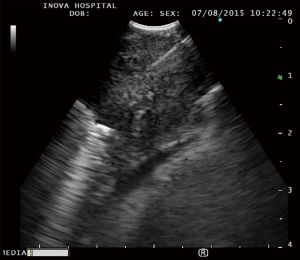

The American College of Chest Physicians (ACCP) recommendation for the mediastinal staging of patients with non-small cell lung cancer endorses EBUS bronchoscopy (14). Through real time ultrasound imaging, EBUS provides clear images of lymph nodes and proximal lung masses that can be adequately sampled through transbronchial needle aspiration (TBNA) (Figure 3). EBUS is a minimally invasive, outpatient procedure. Large studies investigating the use of EBUS for mediastinal staging have shown the procedure to be highly sensitive (93%) and specific (100%) while harboring an excellent safety profile (15). Pulmonologists with extensive training in performing EBUS bronchoscopy are capable of accurately staging the mediastinum by sampling lymph nodes as small as 5 mm. When peripheral lung nodules are sampled using ENB, the use of EBUS to stage the mediastinum is virtually always performed during the same procedure. As a result, unlike TTNA which does not offer access to mediastinal lymph nodes, advanced bronchoscopy utilizing EMN and EBUS to diagnose and stage lung cancer is the ideal to biopsy lung nodules identified through lung cancer screening.